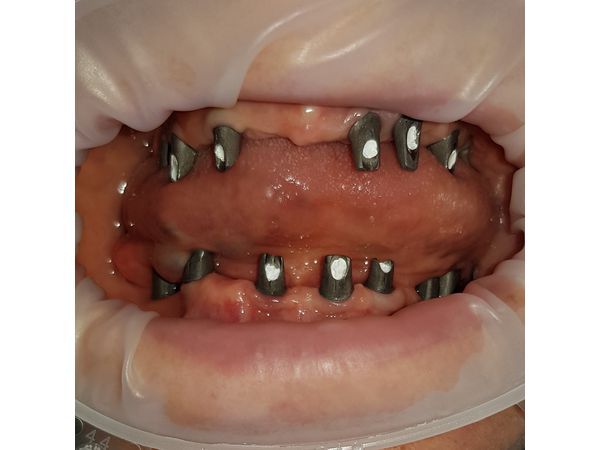

На первом хирургическом этапе была проведена дентальная имплантация на верхней челюсти и через несколько недель на нижней челюсти.

Через месяц установлены временные съёмные протезы. Через 4 месяца после приживления имплантатов выполнено протезирование несъёмными мостовидными протезами.